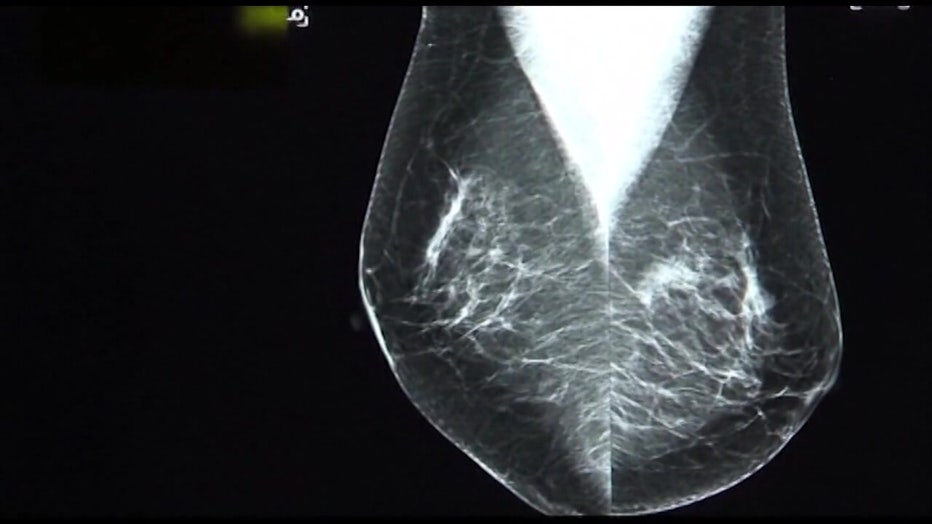

A two-time breast cancer survivor and former Miss Florida USA is urging all young women to look for the signs of the disease. FOX 13’s Danielle Zulkosky reports.

TAMPA - Kristen Berset had it all. Crowned Miss Florida USA 2004, top 10 in the Miss USA pageant and on her way to her dream career as a TV news anchor, but a breast cancer diagnosis stopped her in her tracks and that's why she is encouraging all women to know the warning signs.